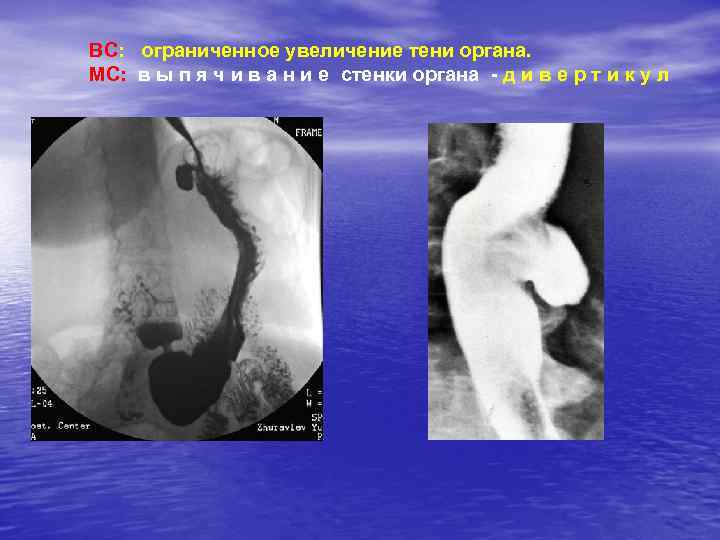

ВС: ограниченное увеличение тени органа. МС: в ы п я ч и в а н и е стенки органа - д и в е р т и к у л